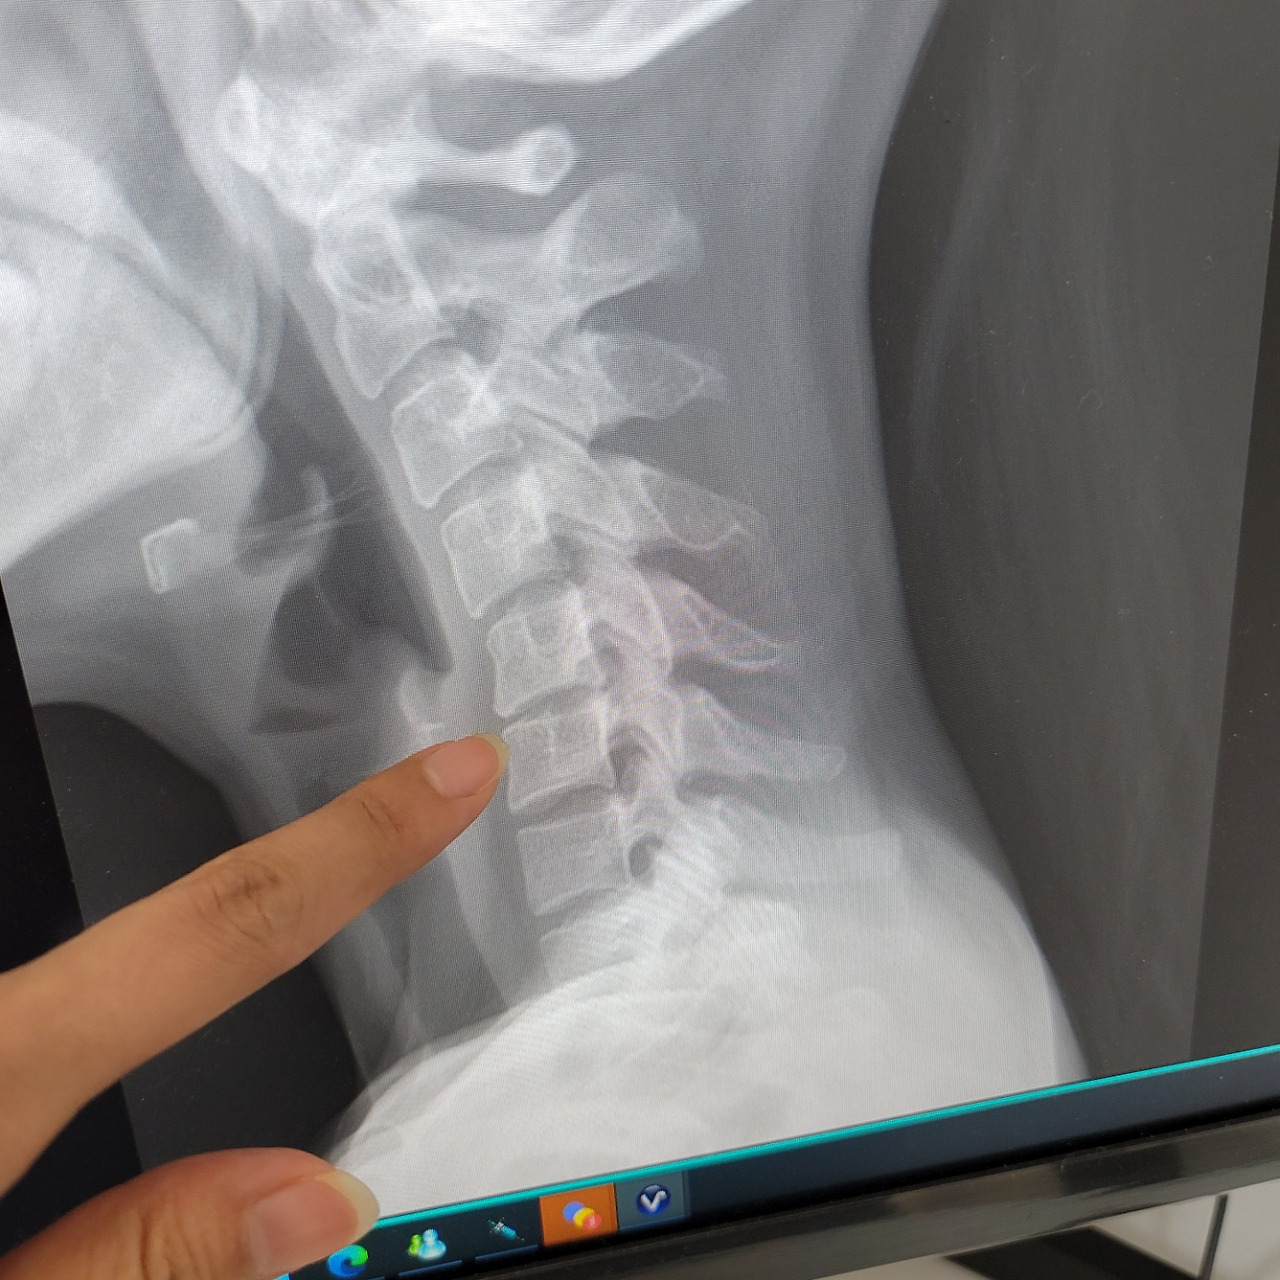

정형외과를 다녀왔다. 목이 거북이가 되었다고 한다. 삶도 느릿느릿 거북이인데;ㅋ 목도 거북목이었구나..ㅎ 거북목이 많이 심해서 43도의 커브가 있어야 하는데 역커브가 되었다. C자형 이어야하는데 역C가 되었다고나 할까...

거북목 진단을 받은 나. 목디스크에 손까지 저린 나. 무엇을 얼마나 바라왔기에 그렇게 살아왔을까? 더더더더가 아닌, 적당히적당히적당히로 살고자 한다. 내몸맘 회복훈련을 위해 80% 정도 했을 때 의도적으로 잠시 쉬었다가 가려고 한다. 적당히의 가치를 사랑할 줄 아는 내가 되어야 겠다.